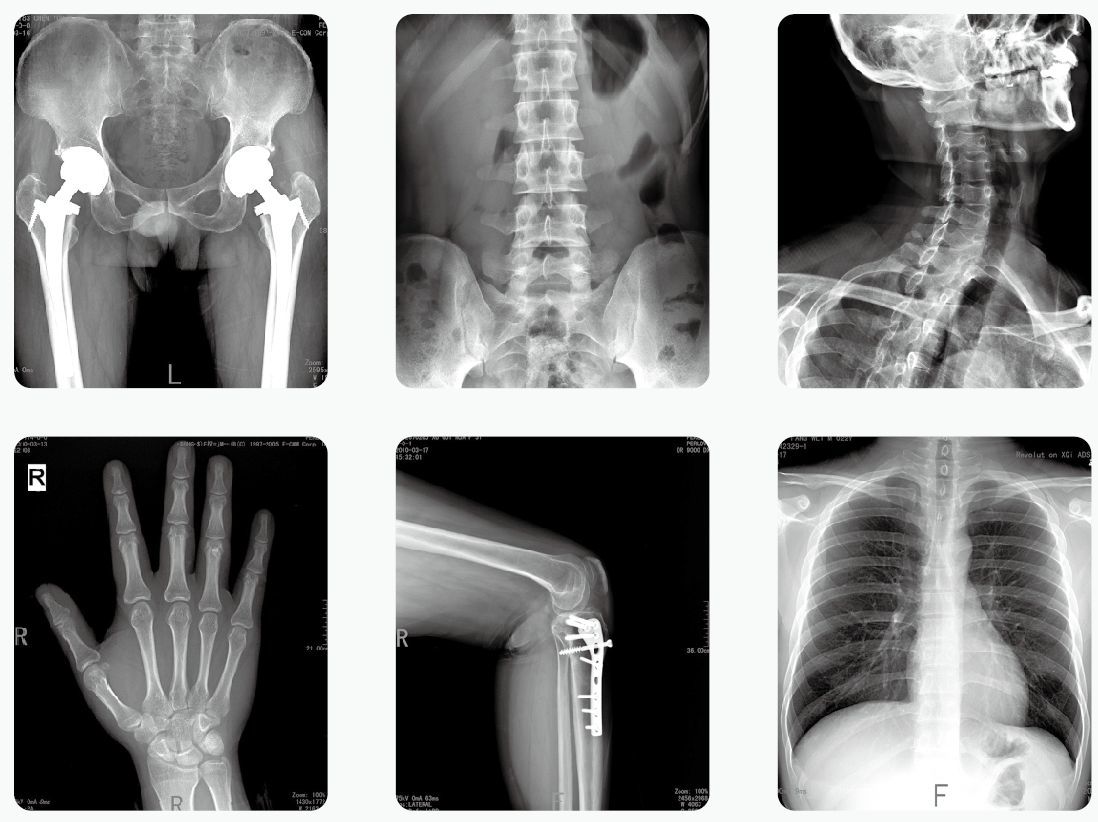

移動式DR為移動式X射線攝影醫療診斷設備,可用于放射科攝影、影像科攝影、兒科攝影、體檢攝影、手術室及重癥監護室攝影,滿足對人體關節、骨骼、胸部、泌尿、婦科和特殊部位的X射線攝影要求。

【產品臨床圖片】